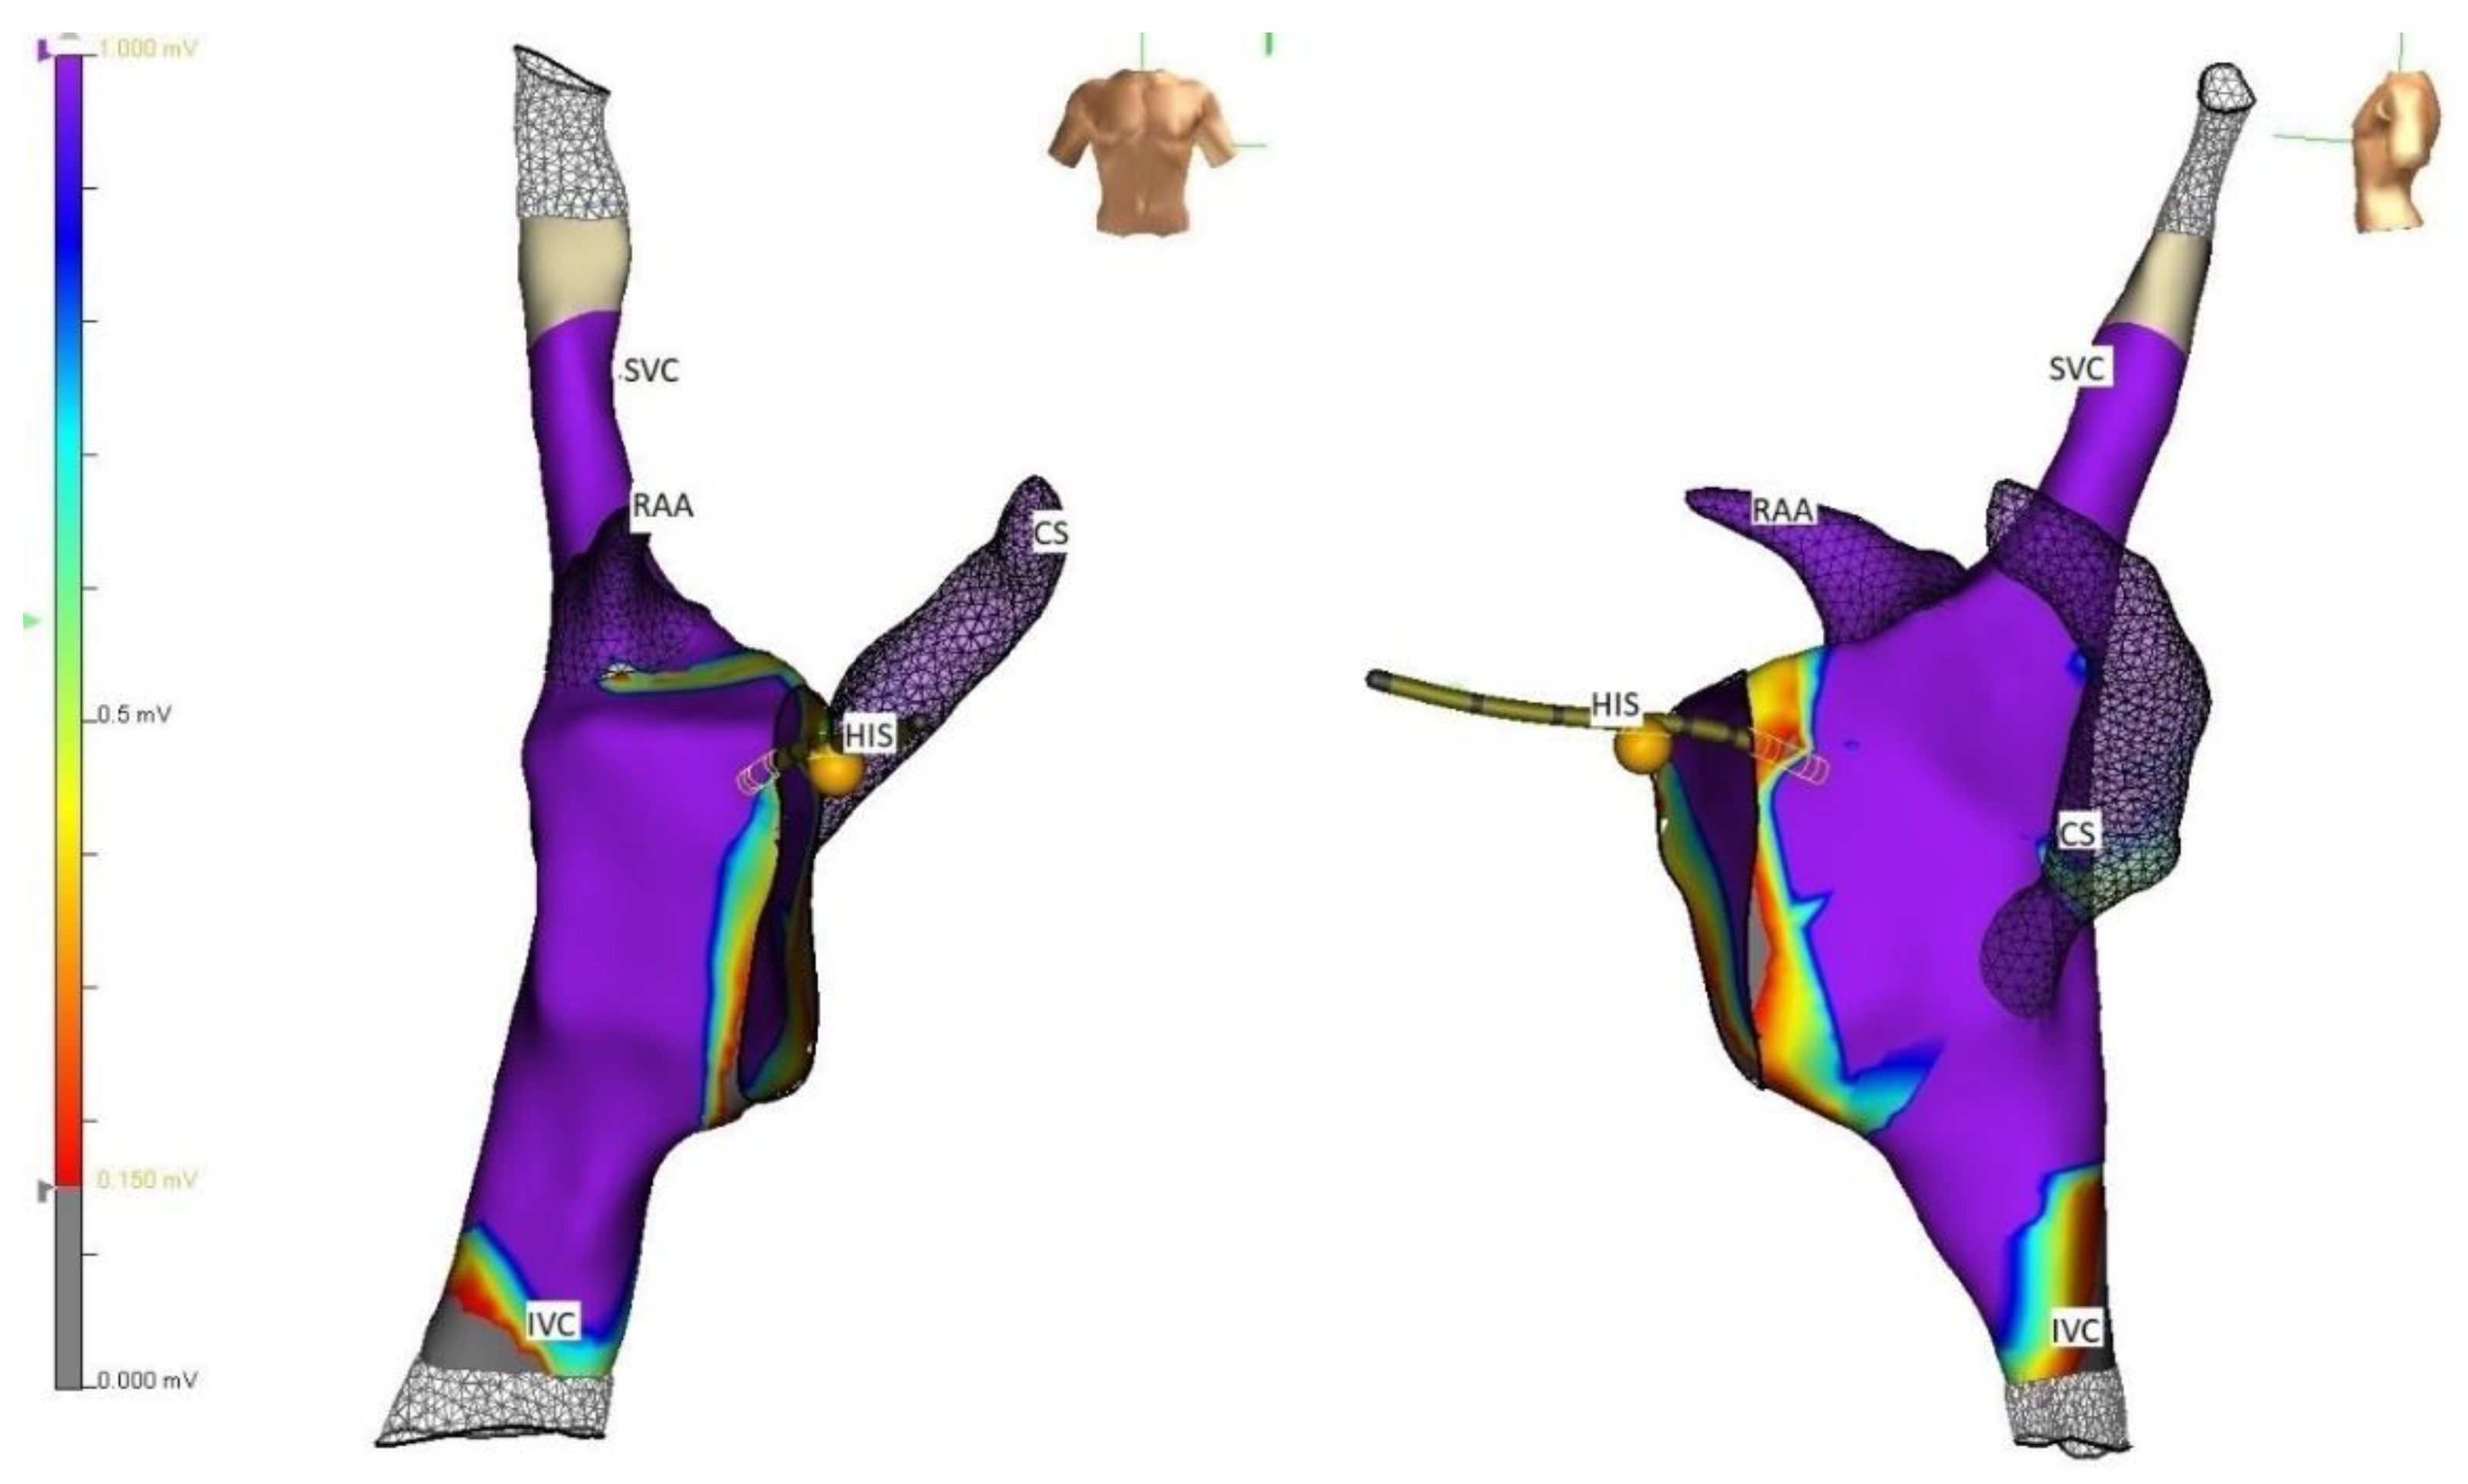

4. Strategies

5. Techniques